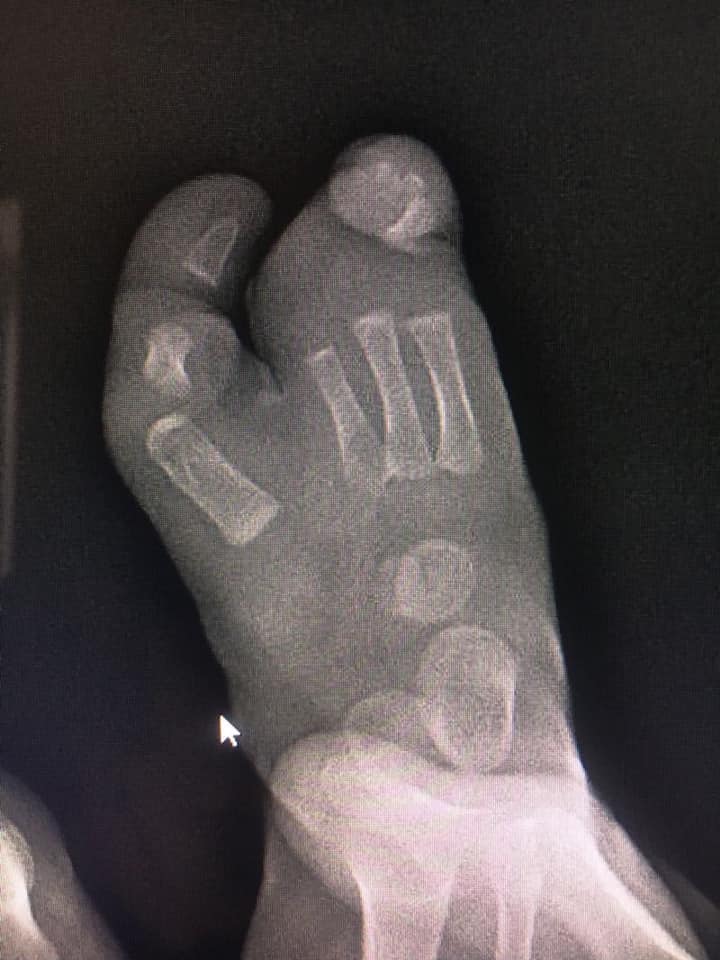

ectrodactilia deformidad en pie

Comparto el caso de mi pacientito Damián, quien me visitó por una deformidad en su pie llamada #ectrodactilia. Tuve la oportunidad de conocer su diagnóstico antes de que naciera, y a los 9 meses le realicé una cirugía de reconstrucción para la alineación del primer dedo, cierre del espacio y alineación del cuarto y quinto dedo. Aprovecho para felicitar a Damián, que hoy cumple 1 año y comienza a caminar sin dolor.